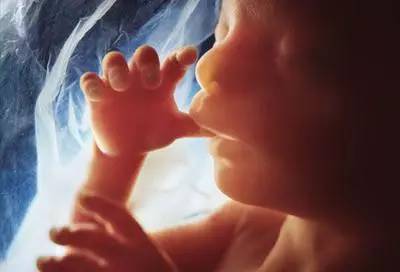

第四个月

胎宝宝身长约16cm,体重约110g。此时已经可以准确辨认出胎宝宝的性别啦。头皮已经开始长出毛发,胎盘形成,胎宝宝开始出现呼吸运动。四肢活动增强,部分孕妈已经可以感觉到胎动了。